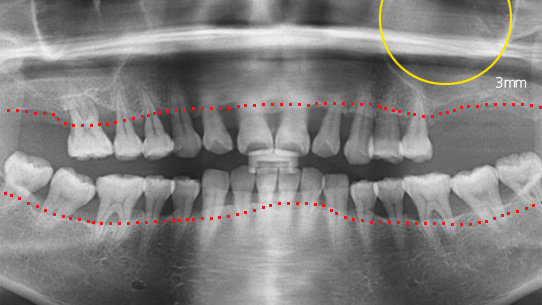

잇몸 염증으로 치조골 손실이 많은 상태

잇몸건강이 회복된 앞니는 크라운으로 수복

심한 염증과 기존 보철물의 오염상태가 심해 다른 병원에서 임플란트 17개 진단을 받고 내원, 특히 앞니부분의 치조골이 많이 약해져 흔들림이 심하여 바로

치주치료를 시행하였습니다. 치주치료 2주 후 앞니 잇몸이 개선되어 발치 하지 않고 교정 유지장치를 이용하여 흔들림을 보완하였습니다.

오염된 보철물을 제거하고 임플란트 11개를 식립하였습니다.